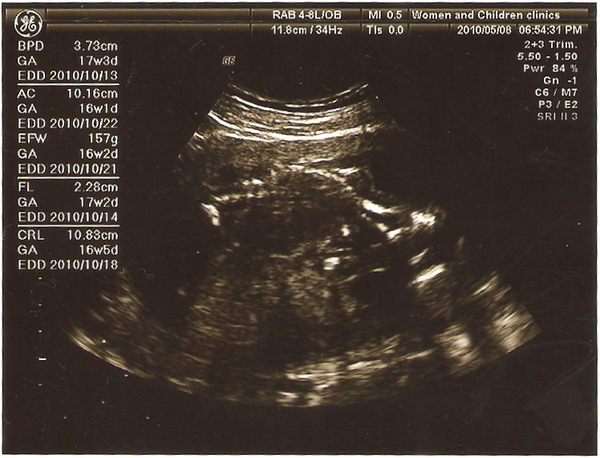

先檢查大腦,腦中線、腦室,嘴唇確認不是兔唇,手指腳指一隻一隻數給我看,都正常

不過跟郭綜合說的一樣,我目前胎盤位置有點低,但是週數還小,繼續觀察就好

小李董長得不錯,頭圍、腿長多出一週,腹圍正常,之後再看有沒有需要校正預產期

看不懂,不過數值看得懂就好